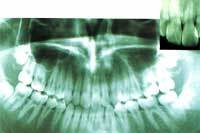

健康な歯槽骨

歯周病で退縮した歯槽骨